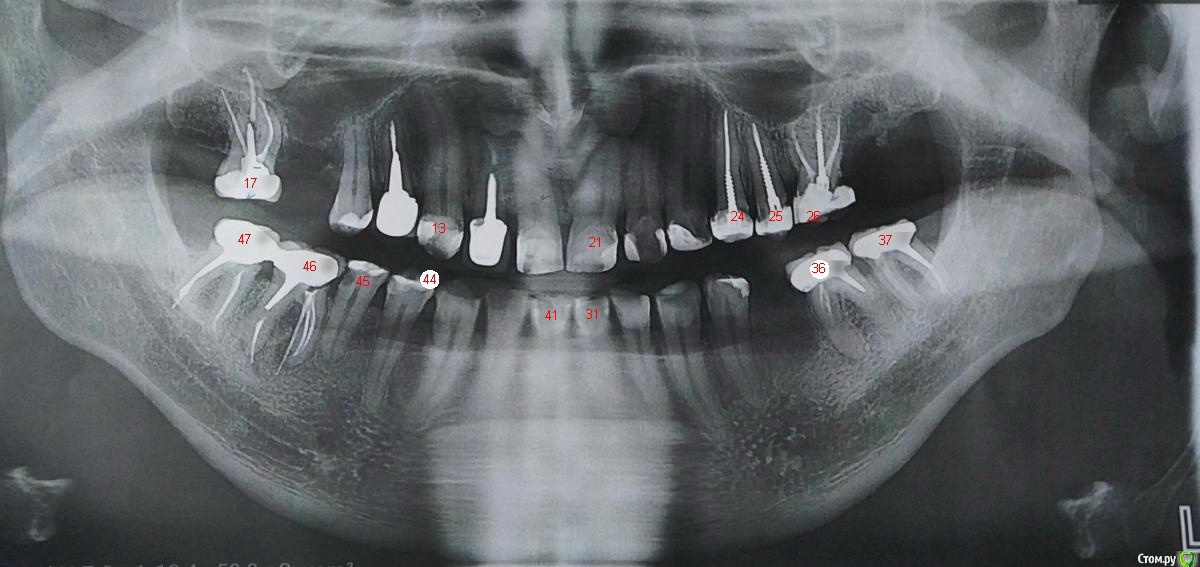

Irouil Опубликовано 1 августа, 2020 Поделиться Опубликовано 1 августа, 2020 Ну ясно. В общем, все фантазии на тему ущемления прав, неоплаченных долгов перед обществом и клиентами, нарушения мифических клятв - тут оффтоп. Этот раздел - для консультирования пациентов по КОНКРЕТНЫМ клиническим вопросам. Таких, на данный момент, 2 1 - отсутствует верхняя правая 6-ка, ее надо протезировать. Судя по предоставленнному орто - показана имплантация с синус-лифтом, возможно раздельно, точнее можно сказать по КТ. 2 - никаких явных проблем с прилеганием коронки на нижней правой шестерке я не вижу, могу так же порекомендовать КТ для контроля пломбировки P.S. мой ник - не МегаЭлита Ссылка на комментарий

Bier Опубликовано 1 августа, 2020 Поделиться Опубликовано 1 августа, 2020 2 - никаких явных проблем с прилеганием коронки на нижней правой шестерке я не вижу, могу так же порекомендовать КТ для контроля пломбировки Коллега, как-то вы странно смотрите.нижний 6й зуб справа (4.6) на удаление. 3 Ссылка на комментарий

Bier Опубликовано 1 августа, 2020 Поделиться Опубликовано 1 августа, 2020 а вот тут совсем не согласен,это государственное высокотехнологичное учреждение с передовыми технологиями и специалистами,это наше с Вами богатое государство и его гарантии на качественную медицину,так сказано на сайте, так и должно быть на самом деле,опять таки, высокий прайс не гарантия результата, у меня в семье с советского союза понимание "врач всегда прав, ему виднее", которое мне с детства прививали,доля сомнения была всегда, и с годами она только росла,Леха, о каком советском союзе идет речь, если вы совсем молодой? Вы даже не знаете, что это такое. Теперь по существу вопроса: на заборе тоже много чего написано, но у вас не возникает сомнений, что это расходится с действительностью. Вот так же и с гос поликлиниками. Единственная цель таких учреждений - избавить вас от боли. Там нет ни высоких/передовых технологий ни специалистов. Что касается вашего плана лечения:17з (верх право 7й) - посмотреть внимательнее на коронку во рту. Мне она не нравится по снимку, но для поликлиники сойдет.16з - синуслифтинг и имплантация.14-? с коронкой13,12,11,21,22,23 - слеплены из пломб, потеряли анатомию требуют реставрации тонкостенными керамическими коронками и/или винирами24,25,26 - снятие старых пломб и штифтов, восстановление коронками.27(верх лево 7й) имплантация36,37 (низ 6 и7) - снятие коронок, перелечивание каналов, новая коронки35з - имплантация34з вопрос к пломбе, возможно под ней вторичный кариес.32,31,41,42,43 - оценка в полости рта45 - глубокий кариес, нужно лечить46,47 - снятие коронок, действительно прилегание нарушено, в 46з с вероятностью 99% перфорация корня и он подлежит удалению с последующей имплантацией.47 переделка коронки. Ну вот это будет современный и передовой подход к лечению. А качать свои права в поликлинике бесполезно. Зубов от этого не прибавится. 3 Ссылка на комментарий

Bier Опубликовано 1 августа, 2020 Поделиться Опубликовано 1 августа, 2020 ещё один?так и не понял про какой речь вот я вам проставил номера, чтобы было понятнее 1 Ссылка на комментарий